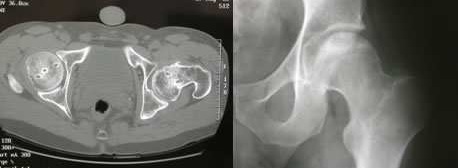

La risonanza magnetica è considerata la metodica d’indagine più accurata per quantificare l’area osteonecrotica in fase precoce e per individuare la sede topografica della lesione, con una sensibilità che oscilla fra 88 e 100 % grazie alle caratteristiche di multiplanarietà e multiparametricità. La RMN, infatti, valuta l’area interessata su 3 piani: trasversale, coronale sagittale ed, inoltre, permette di discriminare la componente ossea da quella cartilaginea, evidenziando un’eventuale condropatia.

In particolare, lo stadio della patologia viene classificato secondo la classification de recherche osseous (ARCO) in 4 livelli basati su reperti radiografici e di risonanza magnetica.